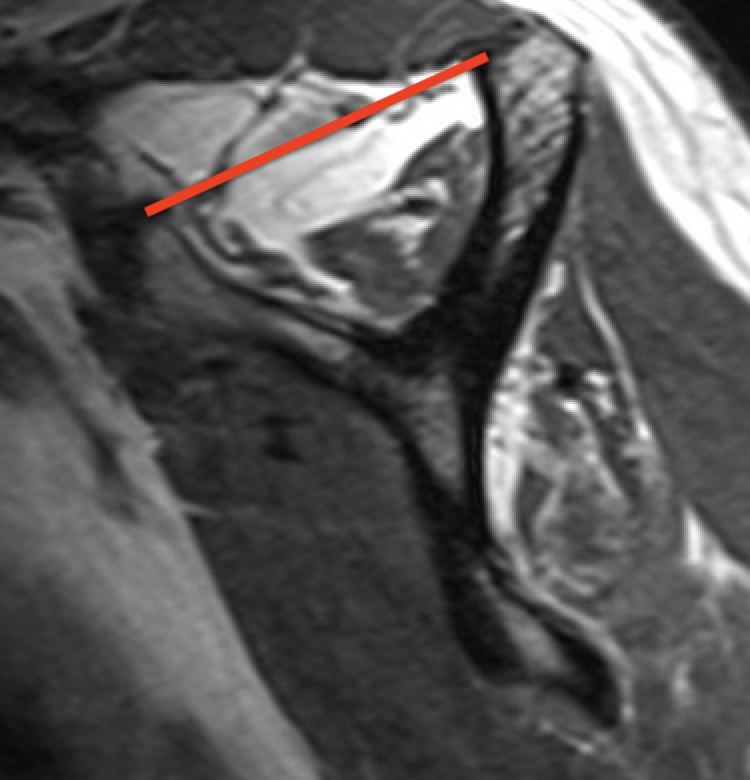

Supraspinatus atrophy

Tangent sign

- sagittal MRI

- line connecting superior coracoid and superior border scapular spine

- if supraspinatus muscle is below line, there is significant atrophy

- positive tangent sign / significant atrophy associated with larger tears / irrepairable tears

Negative tangent / no atrophy Positive tangent / significant supraspinatus atrophy